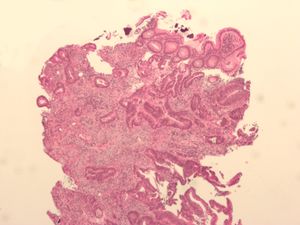

إن الظروف التي تؤدي إلى تهيج الإمعاء، مثل التهاب القولون التقرحي، تزيد من مخاطر الإصابة بسرطان القولون ـ المستقيم. كما تزيد مخاطر الإصابة بالمرض لدى الذين يعاني بعض أفراد أسرهم من هذا النوع من السرطان. وتعرف العلماء على حالات شذوذ في بعض الجينات (المادة الوراثية في الخلايا) المعينة، لها علاقة ببعض الأشكال النادرة للمرض. ويعتقد الخبراء أن العديد من الأنواع الشائعة لسرطان القولون ـ المستقيم، تتضمن أيضًا حالات شذوذ جيني. ويبدأ السرطان غالبًا في السليلة المخاطية، وهي أورام غير سرطانية توجد في الإمعاء. ويتأثر الاستعداد لتكوين السليلات المخاطية، على الأرجح بالجينات أيضًا. قد لا تسبب الإصابة بالسرطان في الجانب الأيمن من الإمعاء الغليظة، خاصة في مراحله المبكرة، أي أعراض ملحوظة. ولكن السرطان الذي يصيب الجانب الأيسر من القولون أو المستقيم، يؤثر في الغالب على عادات التبرز لدى الفرد. ومن ثم، ينبغي على الأشخاص مراجعة الطبيب إذا لاحظوا أي تغيير في عدد مرات التبرز، أو شعروا بأي ألم أثنائه. إن أنواع البراز (فضلات الجسم الصلبة) التي تبدو رقيقة أو رفيعة بصورة غير معتادة، أو التي يشتبه في احتوائها على دم، يجب أيضًا إخضاعها للفحص.

- تنظير القولون: يستخدم تنظير القولون أنبوبًا طويلاً ومرنًا ورفيعًا يتصل بكاميرا فيديو وشاشة لعرض القولون والمستقيم بأكملهما. إذا تم العثور على أي مناطق مشتبه في إصابتها بالمرض، يمكن للطبيب تمرير الأدوات الجراحية من خلال أنبوب لأخذ عينات من الأنسجة (خزعات) لتحليلها وإزالة السلائل.